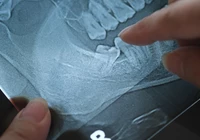

“아프지 않은데… 사랑니 지금 꼭 뽑아야 하나”

사랑니는 20대 전후에 맹출되지만, 매복되거나 부분적으로만 보이는 경우가 많아 주기적인 검진이 필요하다. 사랑니에 충치, 염증, 낭종, 종양이 동반될 수 있으며, 통증이 없더라도 방사선 검사를 통해 확인해야 한다. 위턱 사랑니 발치 시 상악동 천공, 아래턱은 신경 손상 등 합병증 발생 가능성이 있으며, 20세 전후에 발치하는 것이 합병증 발생률을 낮출 수 있다. 고혈압, 당뇨병 등 전신질환 환자는 발치 전 치과 상담 필수.